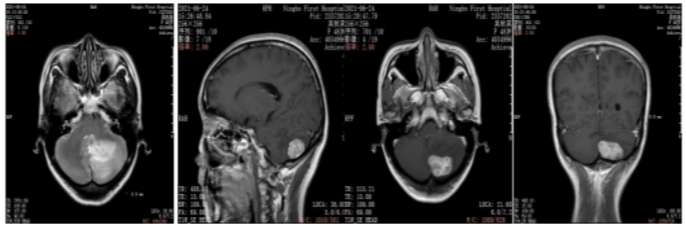

2021年6月颅脑增强MRI:左侧小脑占位,考虑转移瘤。

图2.颅脑增强MRI

2021年6月:出现头晕头痛1周,检查颅脑增强MRI:左侧小脑占位,考虑转移瘤。

2022年5月颅脑增强MRI:左侧小脑肿瘤切除术后改变。

疗效评价CR,继续维持曲妥珠单抗(汉曲优)+吡咯替尼+卡培他滨治疗方案

图3.颅脑增强MRI